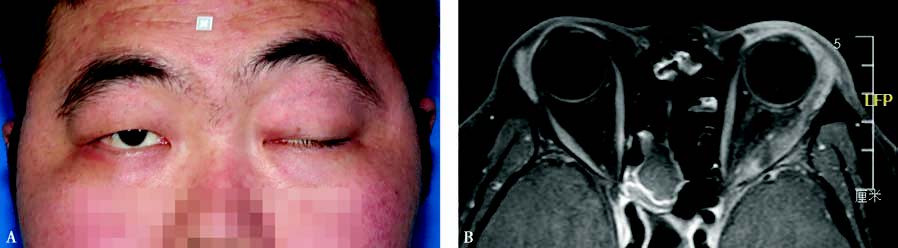

Figure 1 Myositis of the left orbit

A. Left exotropia, eyelid swelling, and ptosis observed.

B. MRI shows significant thickening of the lateral rectus muscle in the left eye, with involvement of both the muscle belly and the attachment site.